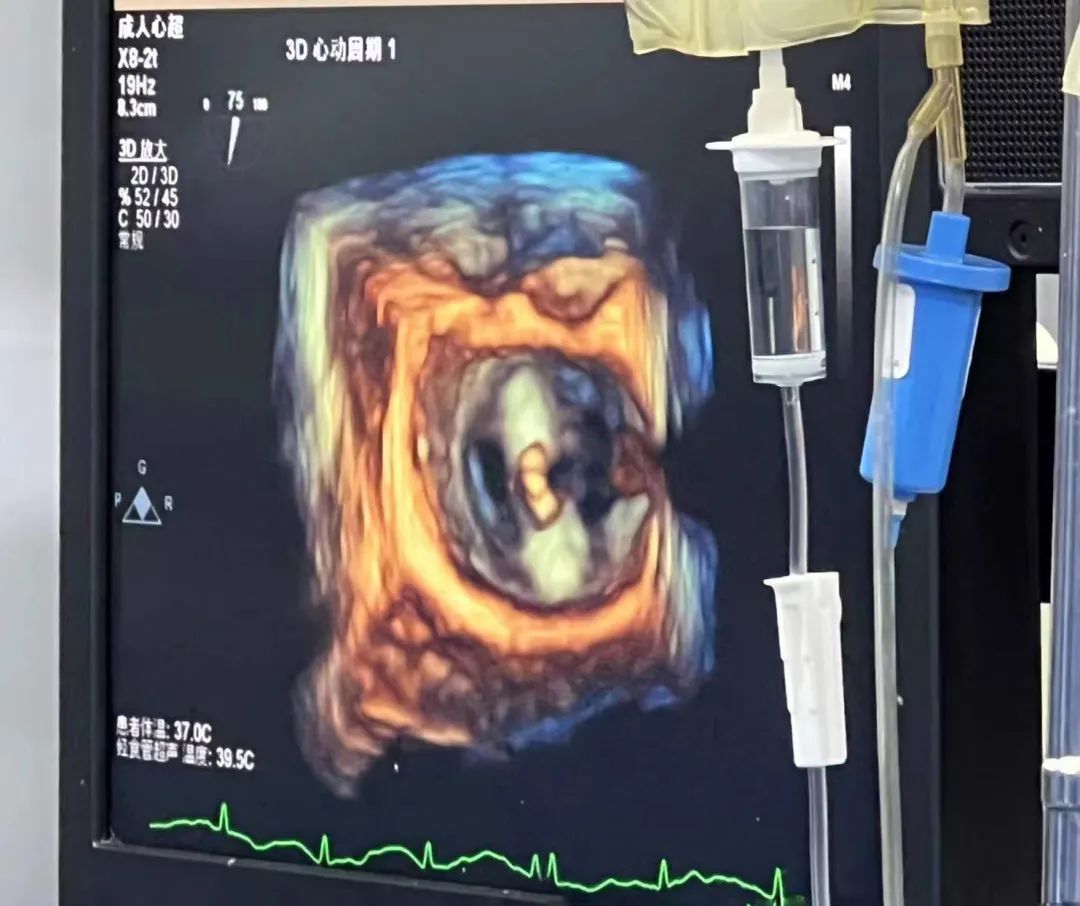

食道超声指导下调整夹合器轴向后缓慢送入左心室

术中,刘宗军带领团队攻克了三大难点。难点一在于,二尖瓣3区紧邻房间隔,操作空间狭小,需要精确选取和定位房间隔穿刺点。难点二在于,3区瓣下腱索丰富,存在乳头肌、肌小梁等复杂结构,操作过程中可能造成腱索断裂等不良事件,会进一步加重瓣膜反流。难点三在于,手术中要持续精准进行超声引导。由于患者二尖瓣病变位于3区靠近后内交界位置,需要超声医生细致微调探头角度以获得清晰优良图像,为术者提供引导。针对这些挑战,手术医生与超声医生密切配合,选择靠上靠后的穿刺点,为后续操作提供足够的空间;食道超声引导在瓣上精确调整轴向,避免瓣下调整可能引起的腱索缠绕,用1枚夹子即获得满意的效果。

患者术中食道超声影像实时画面